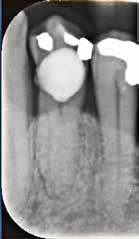

Fig. 1. A. Udsnit af panoramaoptagelse viser Ca(OH)2 uden for foramen apicale i en overkæbemolar og i sinus maxillaris (pil). B. Periapikal optagelse viser Ca(OH)2 uden for foramen apicale (pil) i en central incisiv. Tilfældet krævede kirurgisk indgreb.

Fig. 1 A. An orthopantomography section showing Ca(OH)2 beyond the apical foramen of maxillary first into the maxillary sinus (arrow) and (B) a periapical radiograph with Ca(OH)2 extrusion beyond the apical foramen (arrow) of a central incisor which required surgical intervention.

Ved mistanke om malpraksis vurderer man behandlerens handlinger i alle stadier i relation til opgavens kompleksitet og tager stilling til, om disse lever op til normen for almindelig anerkendt faglig standard. De mest omfattende skadevirkninger ses i forbindelse med anvendelse af endodontiske skyllevæsker og andre medikamenter, fx ulykker med natriumhypoklorit eller skader på nervevæv eller i sinus som følge af udpresning af calciumhydroxid igennem foramen apicale (Fig. 1A og B) (5,6). Sådanne uheld vurderes ofte til at være undgåelige, idet tandlægen ikke har levet op til normal faglig standard. Frygt for at begå procedurefejl eller andre utilsigtede hændelser bør dog ikke få klinikeren til helt at afstå fra at foretage endodontiske behandlinger (7).